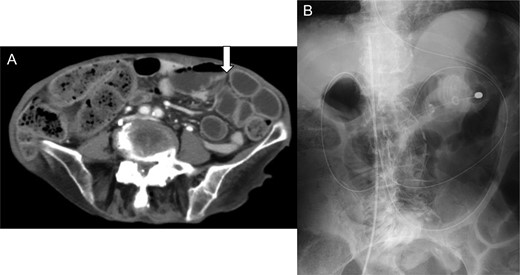

She was given an antibiotic (meropenem 0.5 g, every 8 h), but the next day, the abdominal pain worsened. Laboratory test showed elevation of the inflammation reaction values, and enhanced CT showed free air in the abdominal cavity (Fig. 2A), with increased fluid collection in the anterior space of the bladder (Fig. 2B). We performed emergency laparotomy for suspicion of digestive tract perforation. There was a small hole at the dome of the urinary bladder and another at the peritoneum, and very thick pus extruded into the abdominal cavity. We opened the front part of the urinary bladder, sutured the hole and sutured the bladder to close it. A permanent urinary catheter was placed for bladder drainage and decompression. The postoperative course was uneventful, and the inflammation reaction improved. She was discharged on the 21st postoperative day and had no recurrence since then.

Enhanced abdominal computed tomography 1 day after admission showing (A) free air in the abdominal cavity (white arrow) and (B) massive fluid collection in the posterior space of the urinary bladder (black arrow).